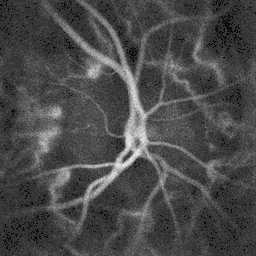

Pulsatile blood flow in the central retinal artery revealed by laser Doppler holography

The central retinal artery supplies blood to all the nerve fibers that form the optic nerve, which carries the visual information to the lateral geniculate nucleus of the thalamus, including those that reach over the fovea. Its blood flow can be revealed by fluorescein angiography or laser Doppler imaging.[4]